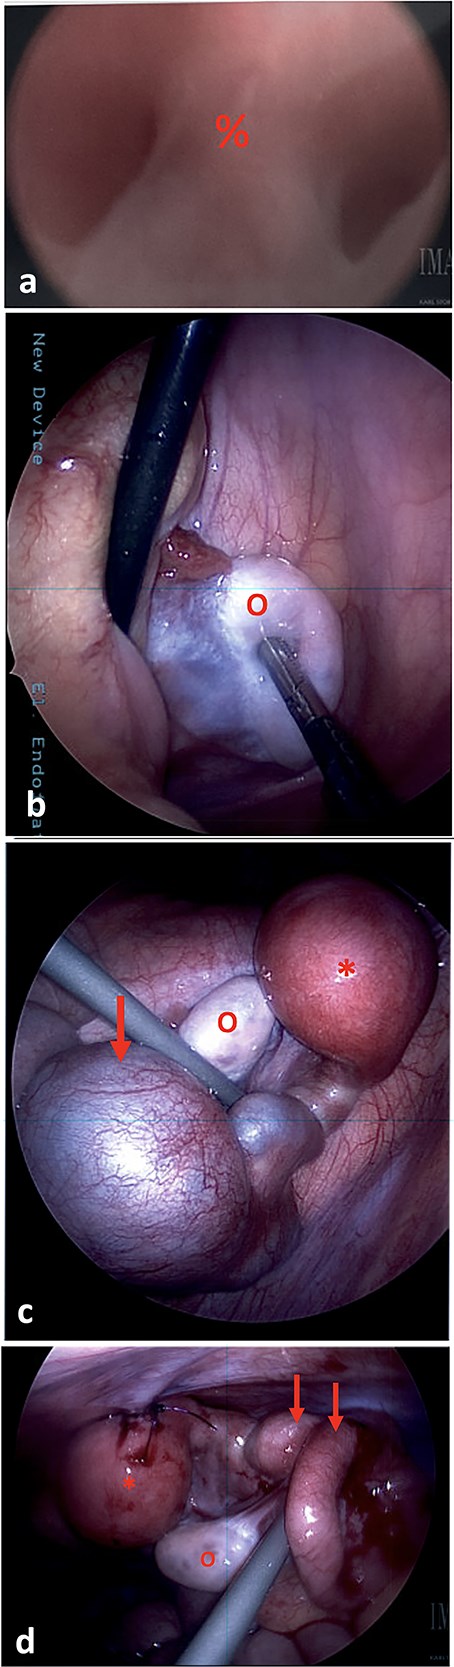

The patient was admitted for a diagnostic cystoscopy, vaginoscopy, and pelvic laparoscopy. An examination under anesthesia demonstrated normal external genitalia, with normal vulvar, urethral, and anal anatomy. A small vaginal dimple was present in the introitus, consistent with vaginal atresia. Vaginoscopy was attempted, but could only be advanced 0.3 cm. A central septum was noted (Fig. 2a). Cystoscopy was unremarkable.

(a) On vaginoscopy, a central septum (%) was noted, suggestive of a longitudinal vaginal septum or hemi-vaginas. (b) Laparoscopic photograph showing the left ovary (o) located in the left lower pelvis, not attached to any tubal structure. (c) Laparoscopic photograph demonstrate a right-sided hypertrophic uterus (*), significantly dilated and firm due to retained blood, and a markedly dilated and tortuous right fallopian tube (arrow). The right ovary appeared normal (o). (d) The uterine dome (*) was sutured to the abdominal wall. The right fallopian tube was decompressed after aspiration (arrows).

During diagnostic laparoscopy, 50 ml of clear serous fluid was aspirated from the pelvic cul-de-sac. A left ovary was present in the left lower quadrant, but no left sided uterine or tubal structures were identified (Fig. 2b). On the right side, a hypertrophic hemiuterus was visualized, significantly dilated and firm due to retained blood (hematometra) (Fig. 2c). The right fallopian tube was markedly dilated and tortuous with a cystic dilation at the mid portion consistent with hematosalpinx. The right ovary appeared normal. No intrabdominal vaginal structures were noted.

The cystic segment of the fallopian tube was laparoscopically punctured and 60 ml of dark blood was aspirated. The uterine fundus was separately punctured and 40 ml of dark blood was aspirated, consistent with hematometra. A 10Fr silicone Foley catheter was inserted into the uterine dome using a hook cautery device. The balloon was inflated, and the uterus was affixed to the abdominal wall with 2-0 PDS sutures (Fig. 2d).